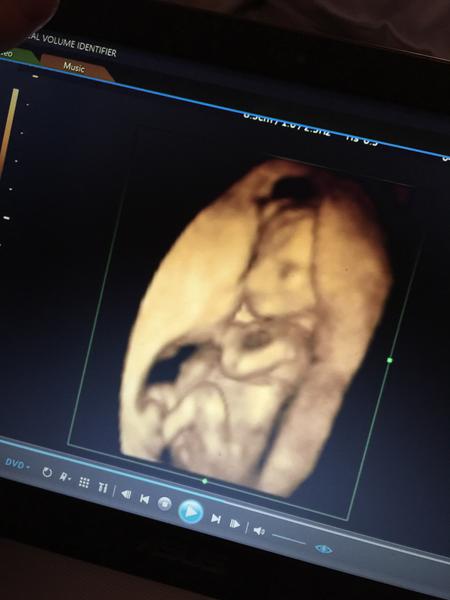

Ahoj maminky a budoucí maminky 😉 Prosím, poradila byste mi některá, co vidíte na fotce z ultrazvuku ve 20. týdnu za pohlaví? Určitě jste foteček viděly už mraky, proto vás žádám o radu...Nechci nikoho ovlivnit, proto svůj tip řeknu později 🙂 Děkuju moc!!!

Myslíte tedy? Mam sice dvě deti,ale jeste ani jednou takto 3D jen u dcerky a to az ve 25 tydnu kdy uz to bylo opravdu videt,ale říka se,že v tom 17-18 tydnu uz by to mělo byt videt 🙂

My máme 2 kluky a ani jednoho takhle hezky ve 3D se nám vyfotit nepodařilo,pak máme holčičku a ta byla na tom 3D podobná tomu Vašemu obrázku. Kluky jsme si nechali říct a opravdu s určitostí nám to řekli hodně brzy, snad i dřív než v tom 17.týdnu.